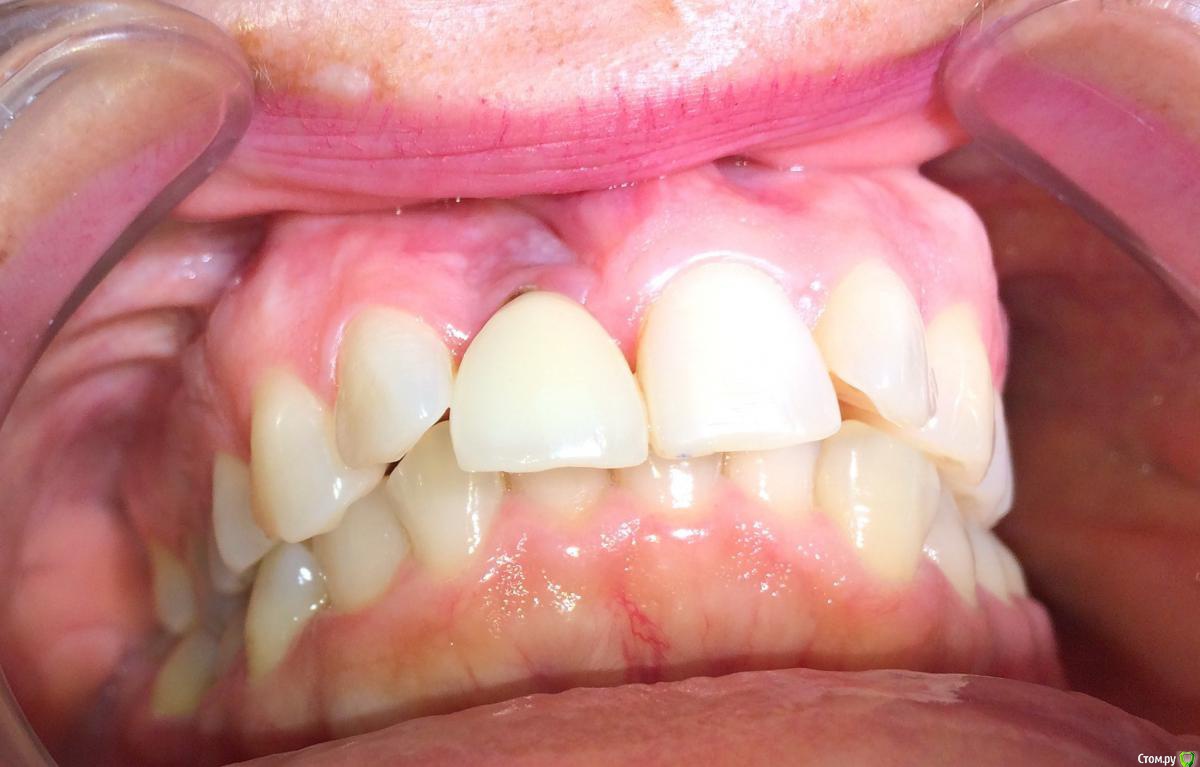

Doctor Vlad Опубликовано 6 сентября, 2020 Поделиться Опубликовано 6 сентября, 2020 Приветствую всех! Такая ситуация. Лет 5 назад имплантация. Кто делал уже не существует. Слизистая в области 11 тонкий биотип. Просвечивается имплант. высокая линия улыбки и выглядит просто темным пятном. Не красиво короче. В прошлом гноилось. Абатмент золотым колечком оголен чутка. кт приложен скрин. Витков 5 вестибулярно не в кости. коронка возможно перегружена прикусомМой план: начать с десны. если эстетически будет удовлетворительно и процесс остановится хорошо. коронку из прикуса вывести ещено остается вариант удаление импланта костная аугментация и десневая и все по новой Ссылка на комментарий

Irouil Опубликовано 6 сентября, 2020 Поделиться Опубликовано 6 сентября, 2020 ИМХО идеальной эстетики тут не добиться, апроксимально тоже выраженная атрофия. Я в таких случаях всегда предлагаю начать с десны+временных чтобы пациент рассмотрел предел возможностей малоинвазивного варианта, но если эстетические требования высокие... 2 1 Ссылка на комментарий

Дмитрий Л. Опубликовано 7 сентября, 2020 Поделиться Опубликовано 7 сентября, 2020 Тёмненькое над зенитом коронки это что? Платформа винта? Ссылка на комментарий

Doctor Vlad Опубликовано 7 сентября, 2020 Автор Поделиться Опубликовано 7 сентября, 2020 Тёмненькое над зенитом коронки это что? Платформа винта?там золотого цвета что-то. скорей всего абатмент Ссылка на комментарий

Дмитрий Л. Опубликовано 7 сентября, 2020 Поделиться Опубликовано 7 сентября, 2020 Угу. И видимо цементная фиксация.Мой план такой)1. Оценить прикрепление, есть ли оно вообще к абатменту хоть в какой то степени. Если десна спокойно отодвигается аж до винта - вскрываем, кюретажим, песочим, НКРим по всем канонам.Если десна прикреплена к абатменту, то можем считать поверхность винта неконтаминированной. Я вижу ряд проблем которые надо решить. 2.Уздечка губы. Слизистая над имплантом кажется подвижной. Возможно из-за того что вы её смещали коронально. Возможно из-за уздечки. Если это так, то первой отдельной операцией чикаем немножко уздечку. 3. Просвечивающийся имплант лучше чем-то перекрыть. Но мне кажется что там больше светит абатмент, чем винт, и что имплант всё-таки глубже. Решается десной. При чём я бы тут пошел снова в 2 пути. Сначала тоннельно, без отслойки по зениту, оставляя прикрепление к абатменту, всунул бы десны апикальней. После стабилизации ситуации уже добавлял бы по зениту и чуть подтягивал бы коронально созданный объём. Швы, которые будут удерживать трансплантат, фиксируйте не над ним, а ближе к соседним зубам, где десна явно кератинизированная. 4. Вцелом наблюдаем перимукозит. Там точно цемента не вывели? 5. Правильней всего было бы снять коронку и вести на узком формике или вообще глухо. Ну так, мои мысли) 2 Ссылка на комментарий